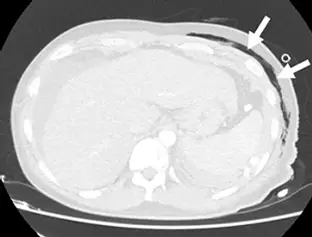

外傷病人的電腦斷層腹部影像如附圖,箭號所指最可能為下列何者?

本題提供一張腹部/下胸部的無顯影劑電腦斷層橫切面影像(採用軟組織窗設定)。

- 解剖構造:影像左側(病患右側)可見肝臟實質,中央可見脊椎與其前方的主動脈,外圍環繞著肋骨與體壁肌肉層。

- 病灶特徵:白色箭號指向病患左側(影像右側)的前外側體壁。該處可見呈現黑色(極低衰減值,與空氣密度相符)的氣體聚積。

- 空間定位:觀察這些氣體黑影的分佈,它們明確位於「肋骨與體壁肌肉層之外」的**皮下脂肪層(subcutaneous fat layer)**之中,呈現不規則的條索狀與氣泡狀透亮區。這些氣體並未進入胸骨內側的胸腔,也沒有進入腹壁肌肉深處的腹腔。

- 綜合判斷:基於氣體所在的表淺解剖位置與密度特徵,此為典型的「皮下氣腫」表現。

根據影像的解剖構造分析,箭號所指的低密度(空氣密度)區域明確位於病患左前外側的皮下脂肪層內,處於骨骼及肌肉構造的表淺處。該氣體並未進入胸腔內部(排除氣胸)、未進入腹膜腔內(排除氣腹),也未處於後方深處的後腹腔(排除後腹腔積氣)。因此,最符合的診斷為皮下氣腫(subcutaneous emphysema),正確答案為 C。